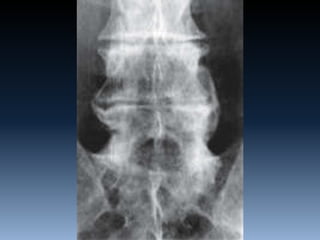

RX TC RMI